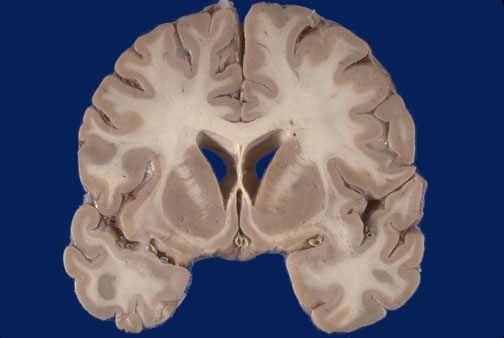

Identify the following regions of the normal brain in the image above: Corpus callosum - Caudate (head) - Putamen - Septum pellucidum - Lateral Ventricle - Temporal Lobe